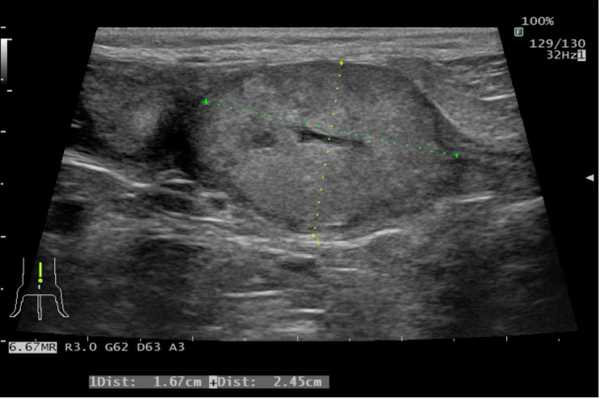

前立腺原発 尿路上皮癌うたがい →外力カテーテル法により得られた尿沈渣をBRAF遺伝子変異検査に外注 →BRAF遺伝子変異陽性 第14病日 CT撮影実施 (図2) →リンパ節、肺、その他臓器への転移所見なし